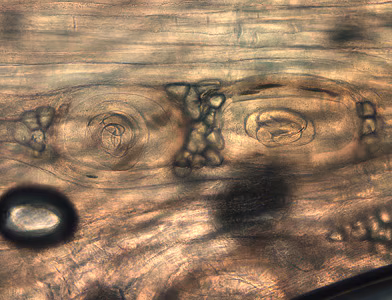

Larvae of Trichinella from bear meat.